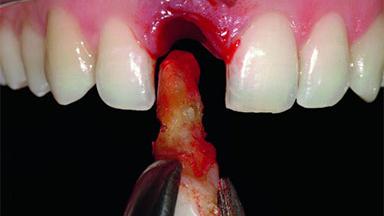

A 32-year-old female Caucasian patient with a compromised maxillary right central incisor was referred to us by a general dentist. Her chief complaints were discomfort and mobility of tooth 11 with unsatisfactory esthetics due to discoloration. The patient reported a previous trauma, some years earlier, as the origin of pathology on the afflicted tooth. Anamnesis was negative for any other dental or periodontal pathology in the remaining dentition. The patient did not take any medication and reported to be a light smoker (5–10 cigs/day). She had high esthetic expectations of her treatment. The extraoral examination revealed a high smile line with full exposure of her maxillary teeth and surrounding soft tissue in the area between the second premolars.

| Bone Augmentation | Horizontal|Simultaneous|Staged |

| Augmentation Materials | Autogenous chips|Xenogenous|Membrane |